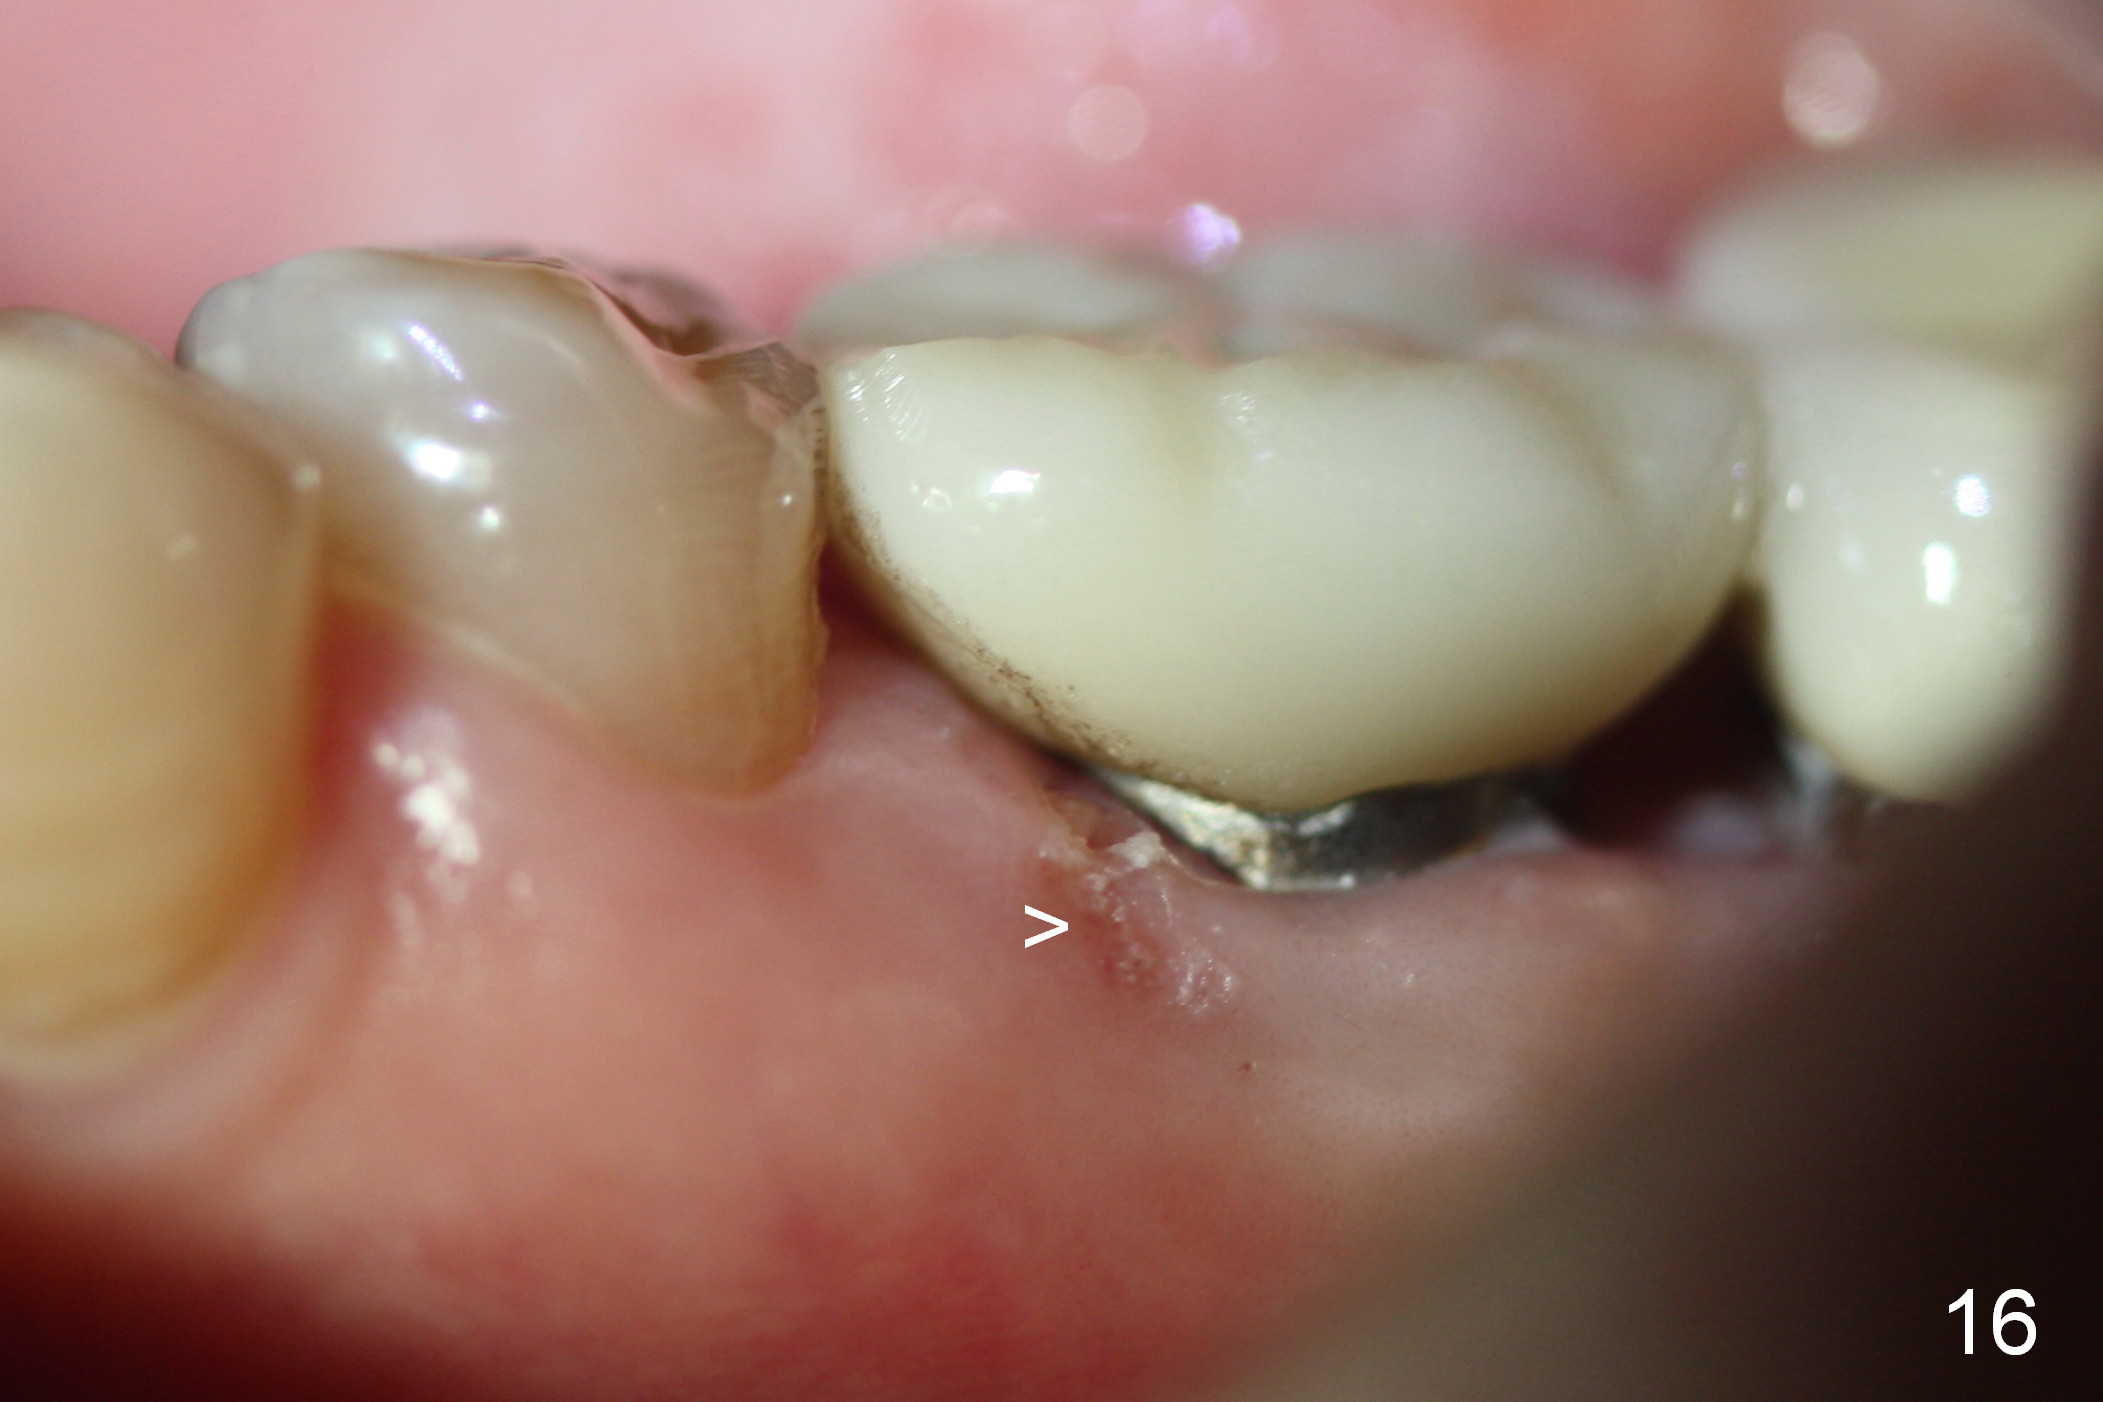

PA taken 3 months postop shows that the distal bone graft (Fig.14 *) appears to consolidate/sink down (arrow) to cover the implant threads. The distal gingiva remains to be fresh granulation tissue less than 4 months postop, immediately before crown cementation (Fig.15 *). The significance of the latter remains to be known. In fact, there is no problem in the distal embrasure. Two and a half months after cementation, the patient returns requesting remaking the crown, since food is easily impacted mesially with floss trauma, as shown by arrowhead in Fig.16.

After removing the crown, the margin is lowered clinically. In the lab, the mesial gingiva in the model is to be trimmed ~1 mm (Fig.17 arrow (black area)) so that the mesial embrasure is closed as much as possible (Fig.18). The contact area is larger both buccolingually and apicocoronally. Clinically, the mesial margin of the temporary crown should be a little bit bulging to push the mesial papilla mesially so that there is enough space to clean cement for the permanent crown.